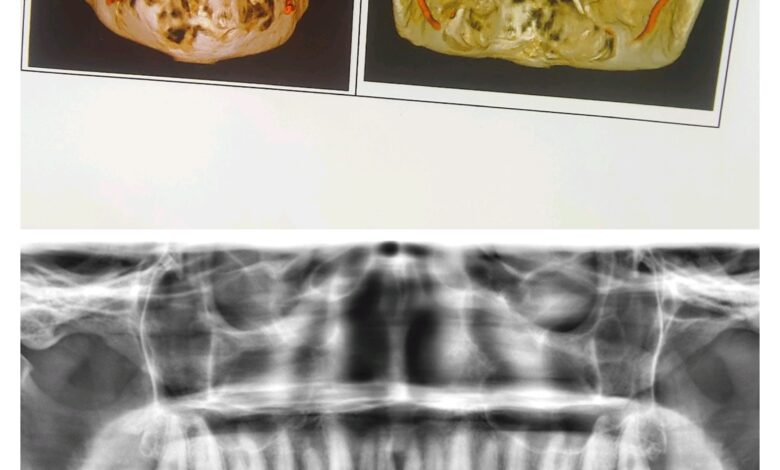

एम्स भोपाल के डेंटल विभाग ने एक बेहद दुर्लभ और जटिल सर्जरी को सफलतापूर्वक अंजाम दिया है। इस सर्जरी के तहत ट्यूमर के कारण काटना पड़ा निचला जबड़ा पैर की हड्डी से दोबारा बनाया गया और उसमें 13 दांत लगाए गए। यह उपलब्धि न केवल मरीज के जीवन में नई खुशियाँ लेकर आई है, बल्कि चिकित्सा जगत में भी एक बड़ी कामयाबी मानी जा रही है। 24 वर्षीय एक युवती मुंह में सूजन और बार-बार पस बनने की समस्या लेकर एम्स भोपाल आई थी। जांच में पता चला कि उसे बिनाइन ओडोन्टोजेनिक ट्यूमर नामक बीमारी है। गंभीर स्थिति को देखते हुए डॉ. अंशुल राय और उनकी टीम—डॉ. बाबूलाल, डॉ. ज़ेनिश, डॉ. सुदीप, डॉ. फरहान, डॉ. प्रधा और डॉ. दीपा—ने बहु-चरणीय सर्जरी करने का निर्णय लिया।

पहला चरण: पहले चरण में युवती के निचले जबड़े को काटकर ट्यूमर को पूरी तरह हटाया गया। ट्यूमर का आकार 12 सेंटीमीटर से अधिक था और उसके साथ 13 दांत भी निकालने पड़े। इस वजह से जबड़ा कमजोर हो गया और दांत भी नष्ट हो गए।

दूसरा चरण: जबड़ा और दांत निकल जाने के बाद युवती को भोजन करने में कठिनाई होने लगी, चेहरा विकृत हो गया और वह अवसाद से जूझने लगी। ऐसे में डॉ. अंशुल राय और उनकी टीम ने पैर की हड्डी (इलिएक क्रेस्ट) से नया जबड़ा बनाकर उसमें 9 डेंटल इम्प्लांट्स लगाए। इसके साथ ही, टीम ने मरीज को मानसिक रूप से मजबूत बनाने के लिए लगातार काउंसलिंग सेशन भी किए।

तीसरा चरण: लगभग 6 महीने बाद जब पैर की हड्डी निचले जबड़े से पूरी तरह जुड़ गई, तब तीसरे चरण में युवती के नए दांत लगाए गए। सर्जरी पूरी होने के बाद मरीज का चेहरा पहले जैसा हो गया, खाने-पीने की समस्या खत्म हो गई और उसका आत्मविश्वास लौट आया। अब वह सामान्य जीवन जी पा रही है और उसकी जीवन-गुणवत्ता पहले से कहीं बेहतर हो गई है।

डॉ. अंशुल राय, जो पिछले 20 वर्षों से डेंटल इम्प्लांट्स और सर्जरी कर रहे हैं, ने बताया कि मध्य भारत में पहली बार 12 सेंटीमीटर का जबड़ा पैर की हड्डी से बनाकर 13 दांत लगाने का यह सफल मामला सामने आया है। इस अनोखे केस को इंटरनेशनल इम्प्लांट्स जर्नल में प्रकाशन हेतु भेजा गया है। डॉ. राय ने कहा कि सबसे बड़ी सफलता यह रही कि लंबे समय से अवसाद में रह रही युवती फिर से सामान्य जीवन की ओर लौटी और उसके चेहरे पर मुस्कान लौट आई।